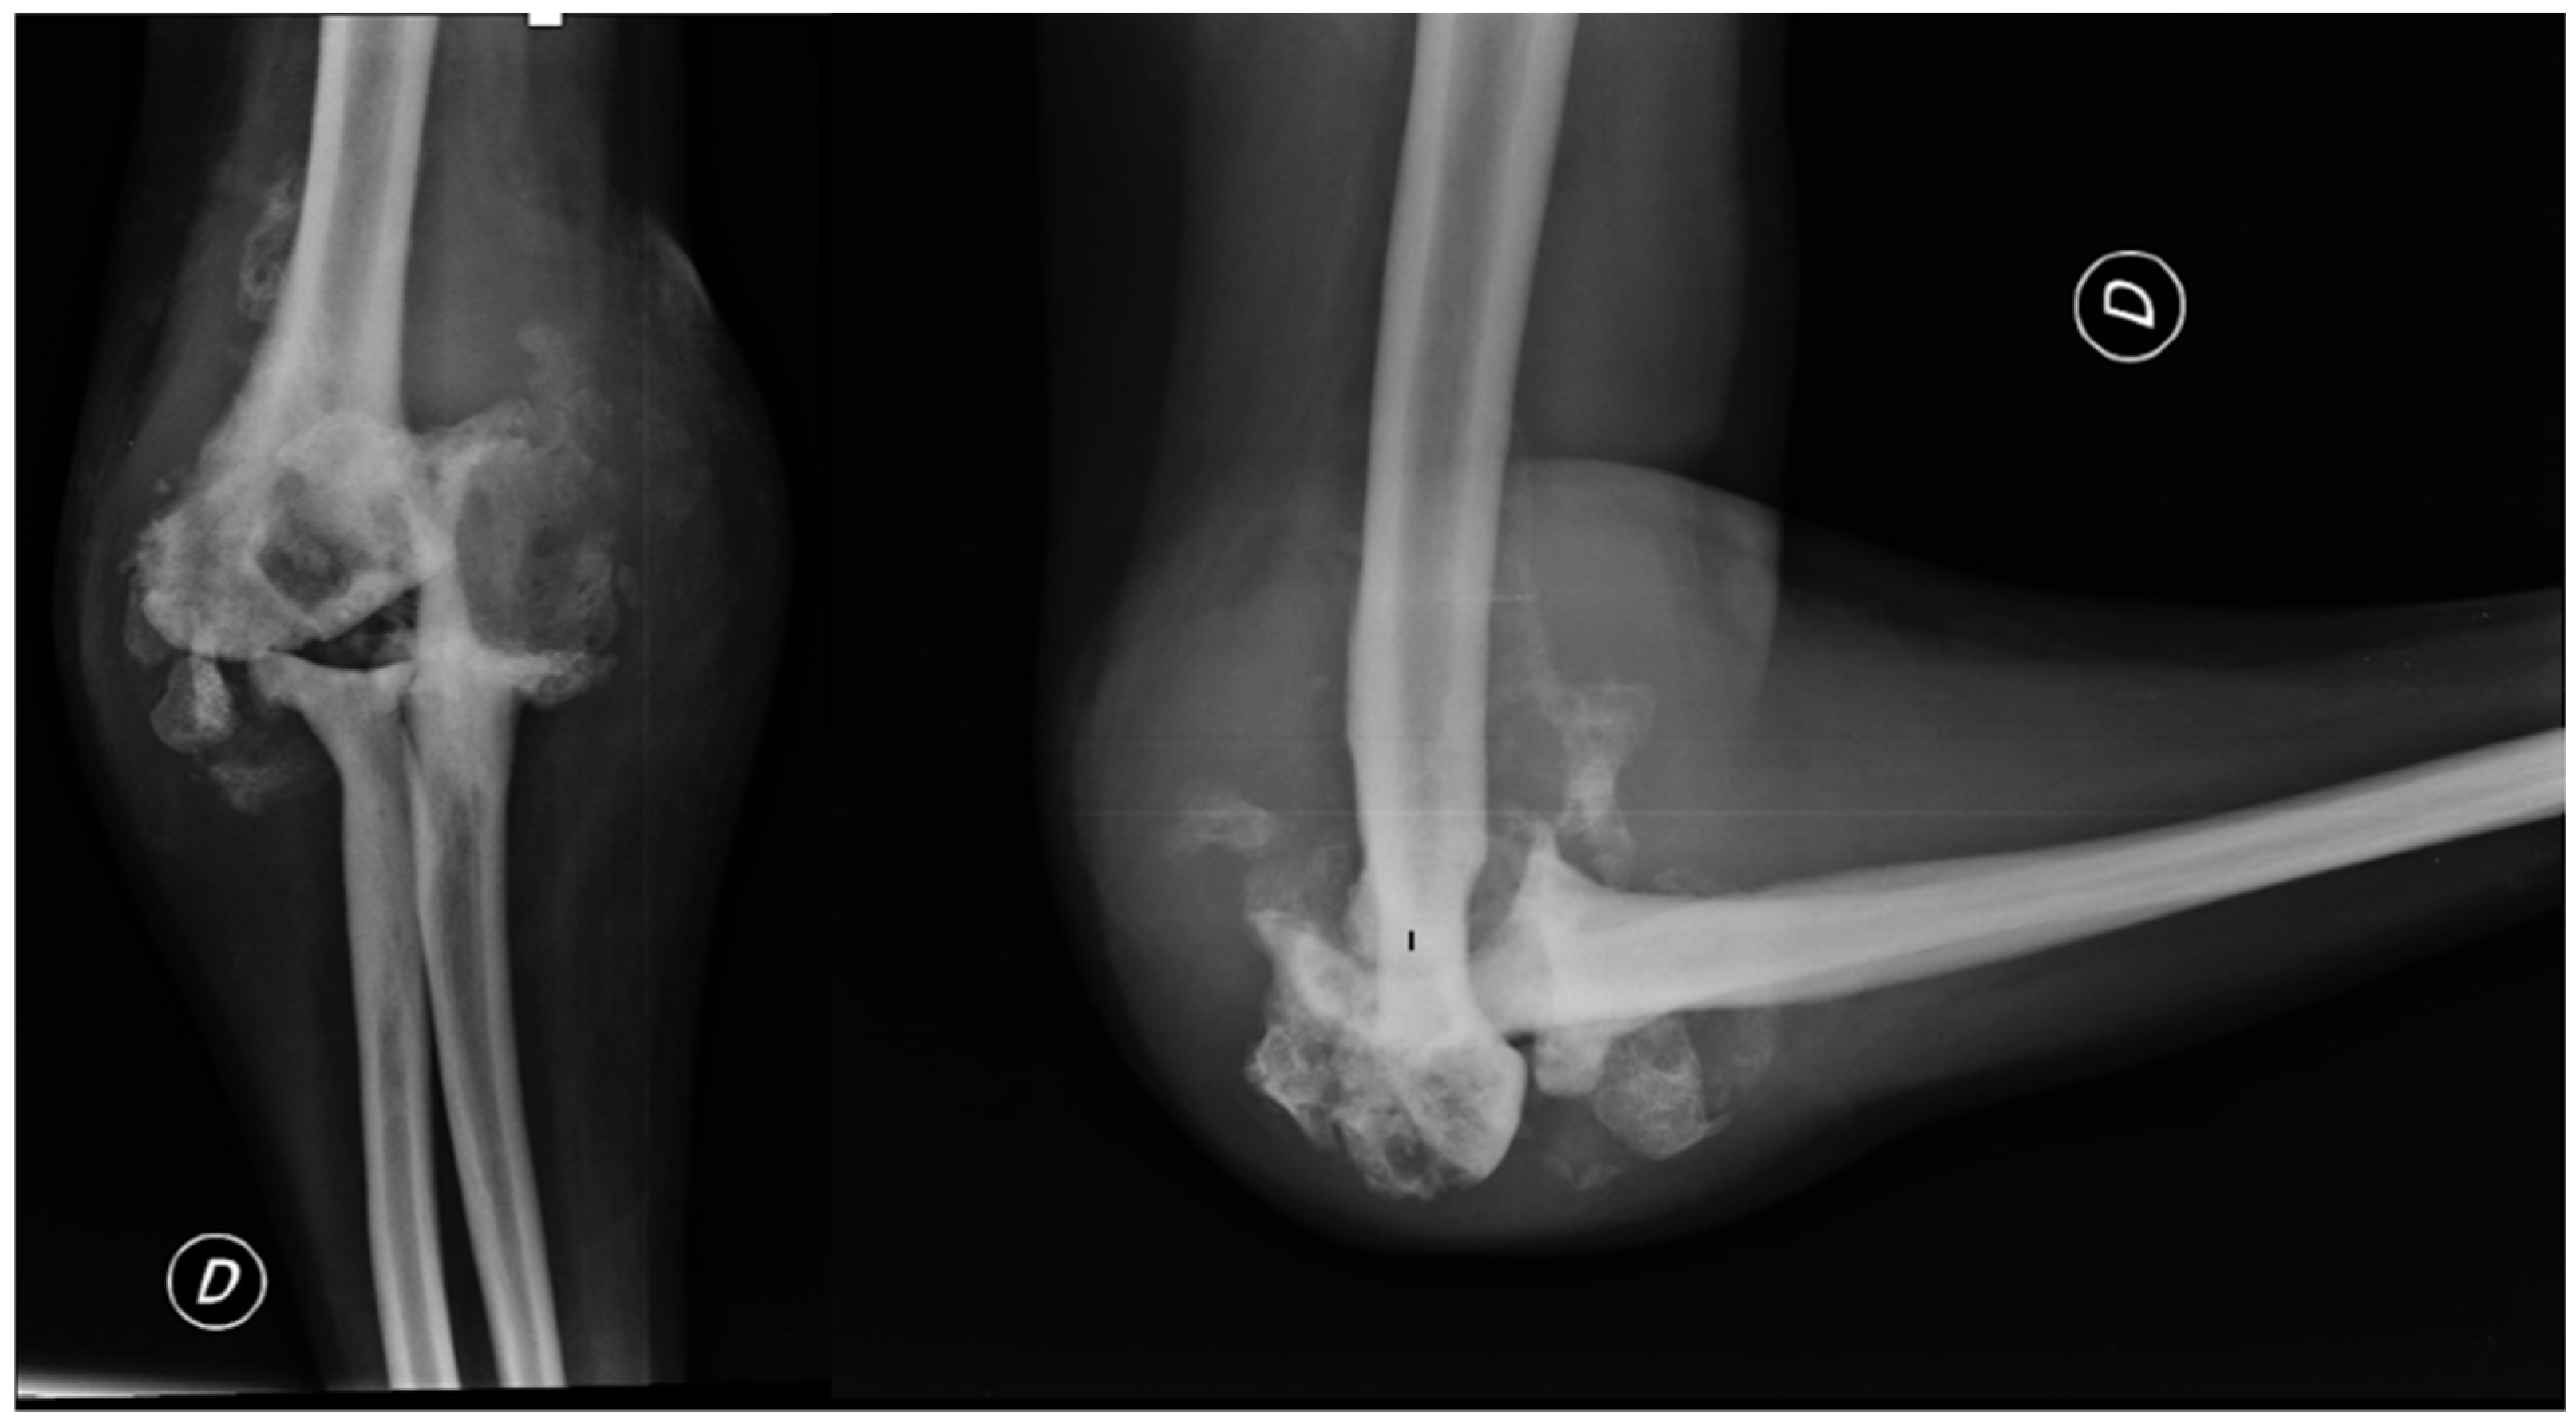

2. Case Presentation

2.2. Clinical Presentation

2.3. Further Investigations